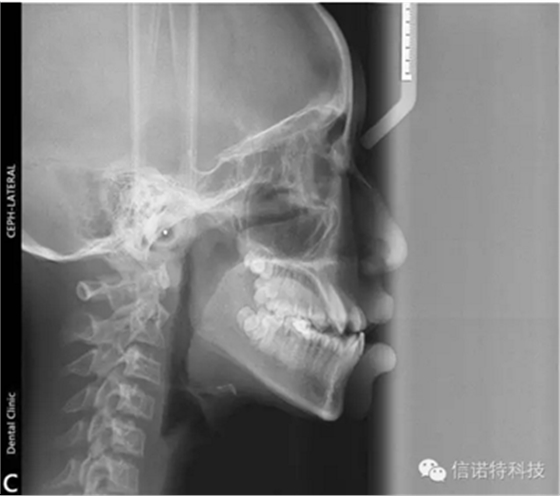

常用X線頭影測量的標(biāo)志點(diǎn)

節(jié)選自《口腔正畸學(xué)》主編:傅民魁 林久祥

蝶鞍點(diǎn)(S.sella):蝶鞍影像的中心。這是常用的一個(gè)顱部標(biāo)志點(diǎn),在頭顱側(cè)位片上較容易確定。

鼻根點(diǎn)(N.nasion):鼻額縫的最前點(diǎn)。這是前顱部的標(biāo)志點(diǎn),代表面部與顱部的結(jié)合處。有些X線片上,此點(diǎn)顯示不太清楚,是因?yàn)槠湫螒B(tài)不規(guī)則骨縫形成角度之故。

耳點(diǎn)(P.porion):外耳道之最上點(diǎn)。頭影測量上常以定位儀耳塞影像之最上點(diǎn)為代表,稱為機(jī)械耳點(diǎn)。但也有少數(shù)學(xué)者使用外耳道影像之最上點(diǎn)來代表,則為解剖耳點(diǎn)。

顱底點(diǎn)(Ba.basion):枕骨大孔前緣之中點(diǎn)。一般此點(diǎn)較易確定,常作為后顱底的標(biāo)志。

Bolton點(diǎn):枕骨髁突后切跡的最凹點(diǎn)。

眶點(diǎn)(O.orbitale:)眶下緣之最低點(diǎn)。當(dāng)病人兩側(cè)對稱及在完好的定位下,左右眶點(diǎn)才于同一水平,但實(shí)際上難以達(dá)到。一般X線片上可顯示左右兩個(gè)眶點(diǎn)的影像故常選用兩點(diǎn)之間的點(diǎn)作為眶點(diǎn),這樣可減小其誤差。

翼上頜裂點(diǎn)(Ptm.pterygomaxillary fissure):翼上頜裂輪廓之最下點(diǎn)。翼上頜裂之前界為上頜竇后壁,后界為蝶骨翼突板之前緣,此標(biāo)志點(diǎn)提供了確定了上頜骨的后界和磨牙的近遠(yuǎn)中向間隙及位置的標(biāo)志。

前鼻棘(ANS.anterior nasal spine):前鼻棘之尖。前鼻棘點(diǎn)常作為確定腭平面的兩標(biāo)志點(diǎn)之一,但此標(biāo)志點(diǎn)的清晰與否與X線片的投照條件有關(guān)。一般不作近遠(yuǎn)中長度測量所用。

后鼻棘(PNS.posterior nasal spine):硬腭后部骨棘之尖。

上齒槽座點(diǎn)(A.subspinale):前鼻棘與上齒槽緣點(diǎn)間之骨部最凹點(diǎn)。此點(diǎn)僅作為前后向測量所用。

上齒槽緣點(diǎn)(SPr.superior prosthion):上齒槽突之最前下點(diǎn)。此點(diǎn)常在上中切牙之牙釉質(zhì)-牙骨質(zhì)界處。

上中切牙點(diǎn)(UI.upper incisor):上中切牙切緣之最前點(diǎn)。一般上中切牙的測量有兩種方法,一種是以此點(diǎn)與根尖相連作為中上切牙牙長軸來作為角度測量的一個(gè)平面,另一種是測量此點(diǎn)與其他結(jié)構(gòu)間的距離。

髁頂點(diǎn)(Co.condylion):髁突的最上點(diǎn)。

關(guān)節(jié)點(diǎn)(Ar.articulare):顱底下緣與下頜髁突頸后緣之交點(diǎn)。關(guān)節(jié)點(diǎn)常在髁頂點(diǎn)不易確定時(shí)而代替髁頂點(diǎn)。

下頜角點(diǎn)(Go.gonion):下頜角的后下點(diǎn)??赏ㄟ^下頜支平面和下頜平面交角之分角線與下頜角之相交點(diǎn)來確定。

下齒槽座點(diǎn)(B.supramental):下齒槽突緣點(diǎn)與頦前點(diǎn)間之骨部最凹點(diǎn)。齒槽緣點(diǎn)(Id.infradentale):下齒槽突之最前上點(diǎn)。此點(diǎn)常在下中切牙之牙釉質(zhì)-牙骨質(zhì)界處。

下切牙點(diǎn)(Li.lower incisor):下中切牙切緣之最前點(diǎn)。

頦前點(diǎn)(P.pogonion):頦部之最突點(diǎn)。

頦下點(diǎn)(Me.menton):頦部之最下點(diǎn)。

頦頂點(diǎn)(Gn.gnathion):頦前點(diǎn)與頦下點(diǎn)之中點(diǎn)。

D點(diǎn):下頜體骨性聯(lián)合部之中心點(diǎn)。

這些標(biāo)志點(diǎn)中,有些是在正中矢狀面上,是單個(gè)的點(diǎn)。如鼻根點(diǎn)、蝶鞍點(diǎn)等。而有些則是雙側(cè)的點(diǎn),如下頜角點(diǎn),關(guān)節(jié)點(diǎn)等。若由于面部不對稱而使兩側(cè)之點(diǎn)不重疊時(shí),則取二點(diǎn)間的中點(diǎn)作為校正的位置。